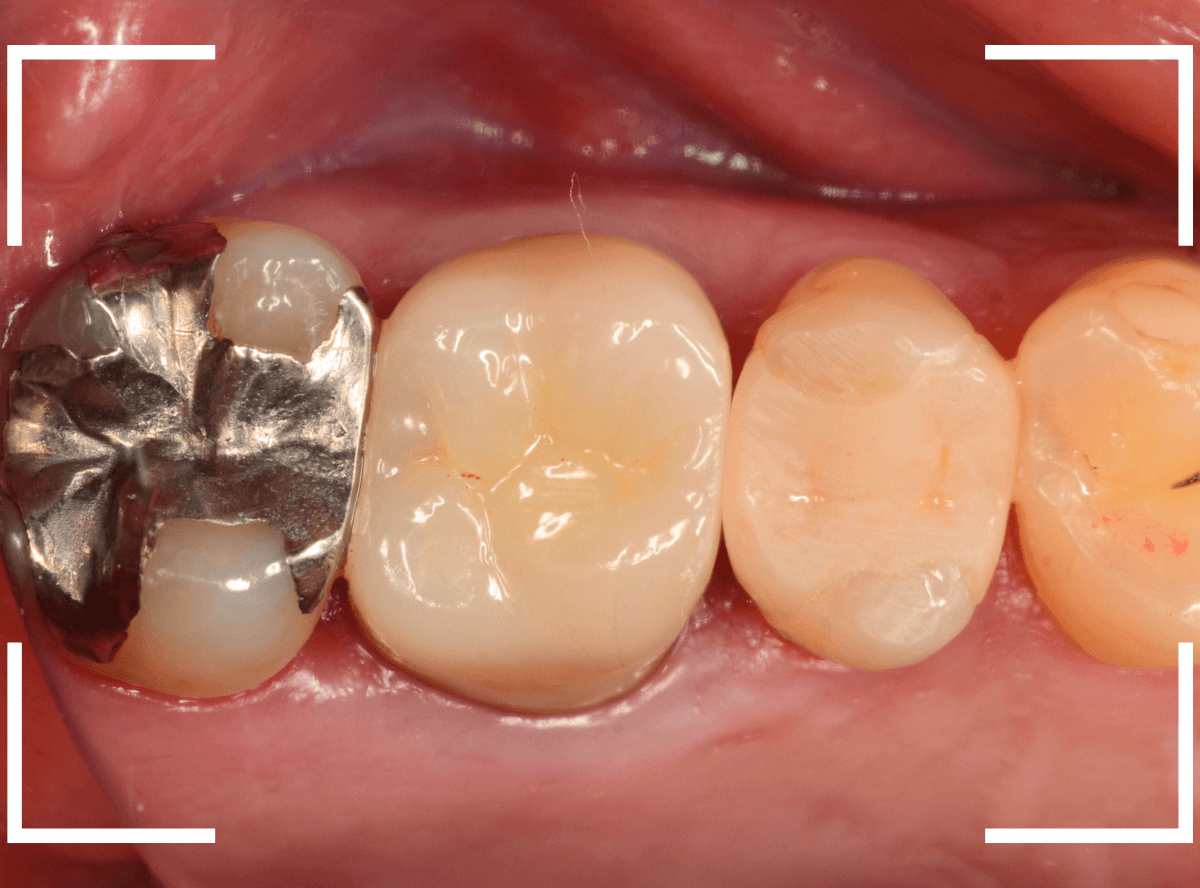

set後の写真です。

患者さんにも満足していただける仕上がりになりました。

治療前後の比較写真になります。